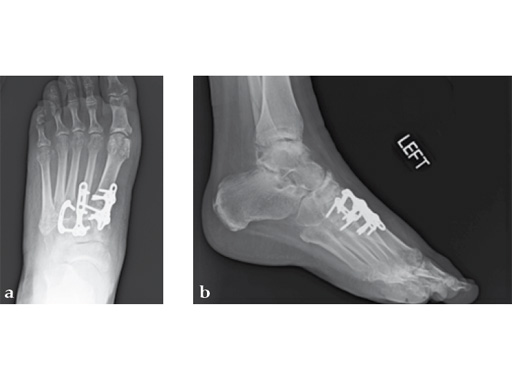

Case 7: VA -locking X-plate

A 49-year-old woman had extreme pain in the talonavicular joint.

As isolated fusion of the talonavicular joint is often hard to achieve, a 4.0 mm lag screw a plus X-plate was used (see Fig. 2a-c).

Fusion of the talonavicular joint while saving the rest of the hindfoot complex motion was achieved (see Fig. 4a-c).